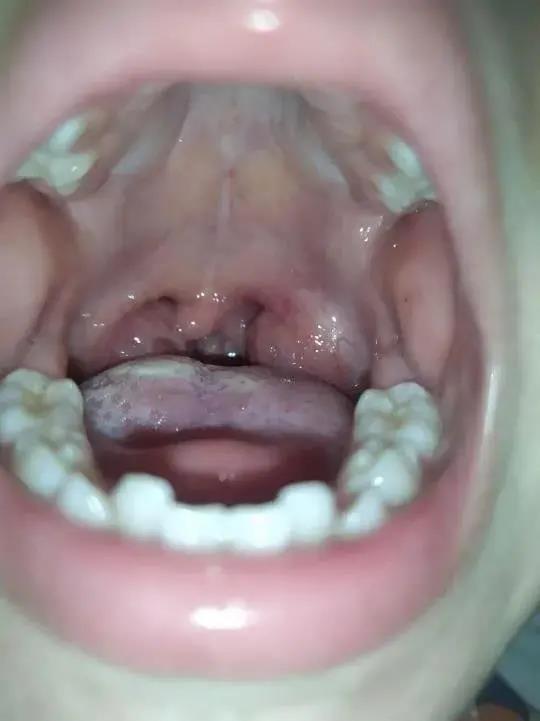

腺样体肥大什么情况下要做手术?

儿童在6岁左右腺样体会增生到最大,到10岁左右开始自然萎缩

听说到10岁后腺样体会萎缩, 那检查出腺样体肥大还有必要手术吗?

确实遇到过一些家长,总觉得腺样体肥大会自行萎缩,孩子腺样体肥大的

小孩腺样体肥大,一定要手术切除吗?